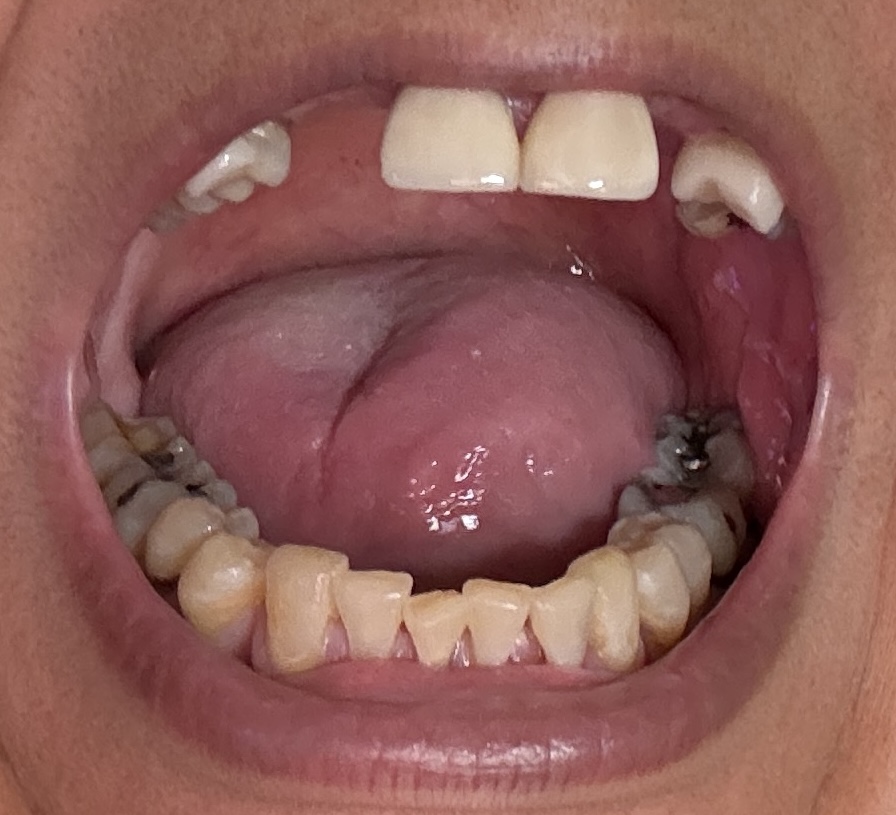

Overall information (upper arch)

12,13,14 have had root canals in past and now have quite a bit movement. 2-5 have all had root canals in past and now the crowns are breaking down.

Overall information (lower arch)

Overall, all of my gums have receded and most of the bottom teeth are exposed w/ some roots and there are many cavities.